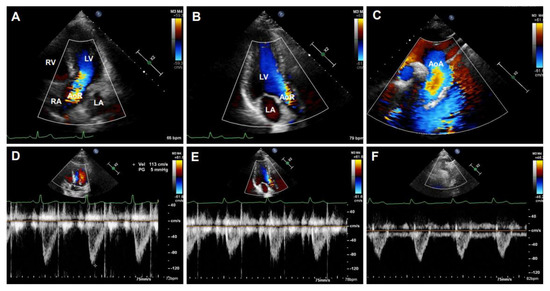

B-mode ultrasonography, also known as two-dimensional (2D) ultrasonography, is one of the most basic ultrasound models that produces a real-time black/white image of the targeted site, where the aortic wall is shown as echo-reflecting and the lumen as echo-free. As shown in Figure 3, the ultrasonographic view of the aorta is either circular in the perpendicular sections or tube-shaped in the parallel sections in humans. For example, the AoR and the AAo could be visualized in the parasternal long-axis view (Figure 3A), the modified right parasternal long-axis view, modified apical five-chamber (Figure 3B), and three-chamber views (Figure 3C). Additionally, the suprasternal view is a crucial view to visualize the AoA and the three supra-aortic trunks (innominate, left carotid, and left subclavian arteries), and a variable tract of the AAo and the DTAo (Figure 3D). In some cases, the entire arch could not be visualized in a single image plane because of the aorta’s extreme tortuosity. The DTAo can also be displayed in the posterior field through the cardiac acoustic window (Figure 3E). Moreover, parts of the DTAo may be invisible due to the tracheal air. The subcostal views may be helpful and allow the DAAo to be visualized (Figure 3F). Although B-mode has been widely used in humans, its application in mouse aorta remains relatively challenging, primarily because of the difficulty in obtaining exceptional spatial and temporal resolution in a small, rapidly varying vessel. Since apical views of the heart are prone to change in rodents, particularly in mice, it is difficult to obtain stable images of the aorta in this view. Reciprocally, the parasternal (Figure 4A), suprasternal (Figure 4B), subcostal, and transabdominal views (Figure 4C) are the most critical views for murine aorta, which enable an adequate assessment of the AoR, the AAo, and most of the segments of the DTAo and DAAo in mouse models.

Figure 3. The representative images of human aorta segments were obtained by B-mode. The segments of the aorta were imaged from a 20-year-old male volunteer. (A): The parasternal long-axis view of the aortic root (AoR). (B): The apical five-chamber view of the AoR. (C): The apical three-chamber view of the AoR. (D): The suprasternal view of the aortic arch (AoA). (E): The parasternal view of the descending thoracic aorta (DTAo). (F): The subcostal view of the descending abdominal aorta (DAAo). LV: left ventricle, LA: left atrium, RV: right ventricle, RA: right atrium.

Diagnostics 11 00454 g003

Figure 4. B-mode imaged segments of a mouse aorta. (A): The parasternal long-axis view of the aortic root (AoR) and the ascending aorta (AAo). (B): The suprasternal view of the aortic arch (AoA). (C): The subcostal view of the descending abdominal aorta (DAAo). LV: left ventricle.

Diagnostics 11 00454 g004